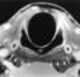

Postcricoid carcinoma